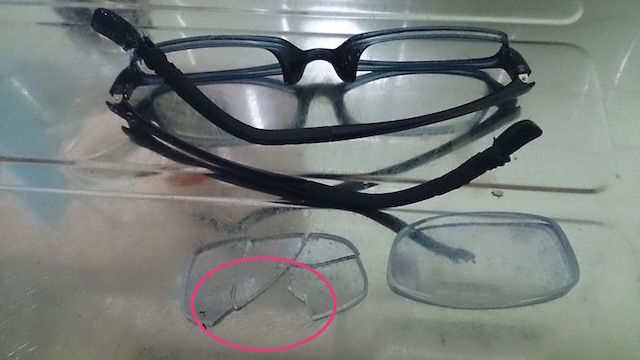

メガネを掛けたまま寝ていたらワンちゃんにメガネをいたずらされ、レンズの破片を合わせると足りないので食べてしまったのかも?

という主訴で来院のあった患者様。

下記がいたずらされたメガネ。ピンクの丸の部分が無くなった部分のレンズです。

内視鏡のポートより把持鉗子を挿入して異物を除去しながら、メガネのレンズのパズルをしていきました。無事パズル完成!!めでたしめでたし!!

皆さん、誤食には注意しましょうね。